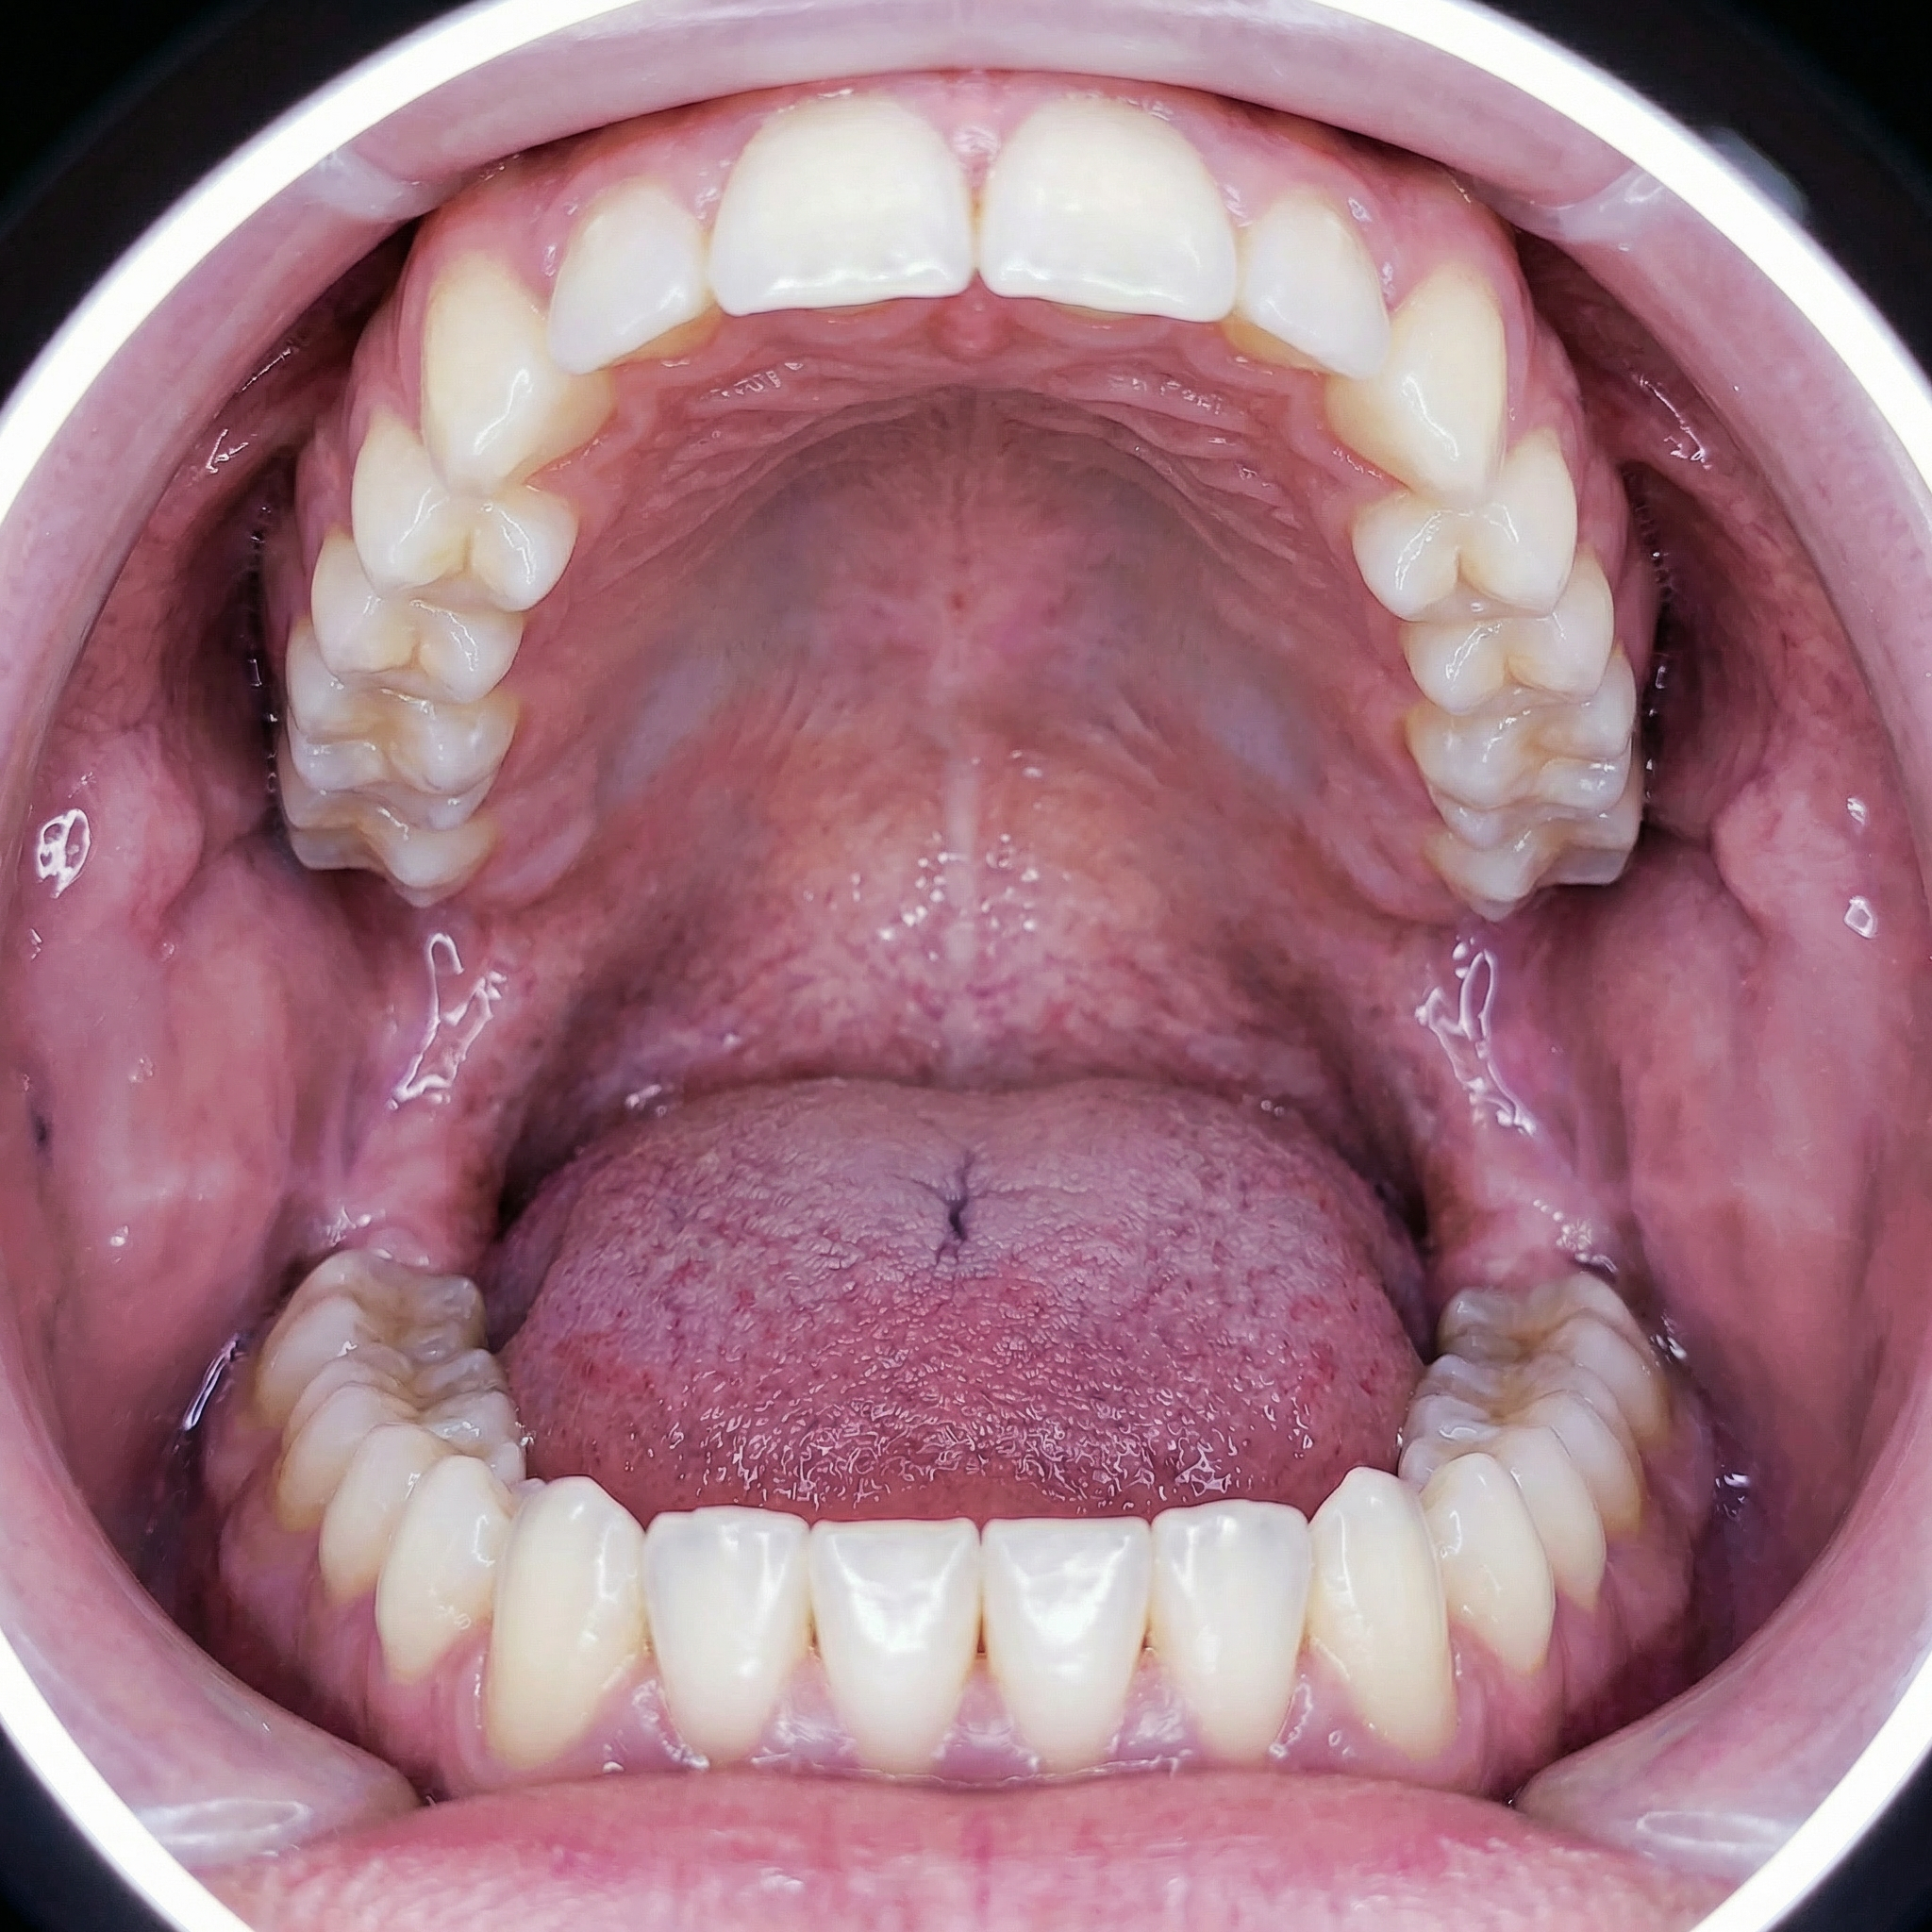

We recruited nine participants for our experimental test. To construct the biofilm, the participants were asked to avoid brushing their teeth for 100 hours.

On the fifth day, let's first look at the basic progress of the biofilm construction (using a biofilm staining agent):

The nine people were then divided into three groups of three. The first group was instructed to clean their mouths using only a toothbrush; the second group was instructed to clean their mouths using only a toothbrush and a tongue scraper; and the third group was instructed to clean their mouths using only the Tongueclear oral hygiene kit. Let's look at the cleaning results: